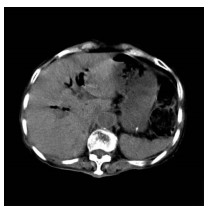

Guideline for ultrasonic diagnosis of liver diseases

Chinese Society of Ultrasound in Medicine, Oncology Intervention Committee of Chinese Research Hospital Society, National Health Commission Capacity Building and Continuing Education Expert Committee on Ultrasonic Diagnosis

2021, 37(8): 1770-1785. DOI: 10.3969/j.issn.1001-5256.2021.08.007

Abstract(3025) HTML (6526) PDF (9311KB)(794)

Abstract:

Ultrasound is a non-invasive, real-time, inexpensive, radiation-free and easily repeatable method, usually used for liver imaging. In recent years, new ultrasound examination techniques for liver diseases such as contrast-enhanced ultrasound and elastography have been rapidly developed, which can effectively identify intrahepatic space-occupying lesions, assess the degree of liver fibrosis and portal hypertension, and monitor the effects of treatment. Therefore, these technologies play an important diagnostic role in clinical liver diseases and have therapeutic interventional value. This guideline classifies the instrument set-up, patient preparation, and physician examination methods through multimodal ultrasound examinations (gray-scale ultrasound, color Doppler ultrasound, contrast-enhanced ultrasound, elastic ultrasound) for liver diseases. In addition, liver diseases multimodal ultrasound technology diagnostic criteria for diffuse hepatic lesions (inflammatory lesions, fibrosis, and sclerosis), multiple space-occupying lesions, and interventional procedures have been defined and standardized. Concurrently, we also recommend the ultrasound monitoring time interval and diagnostic report writing standard for liver diseases.